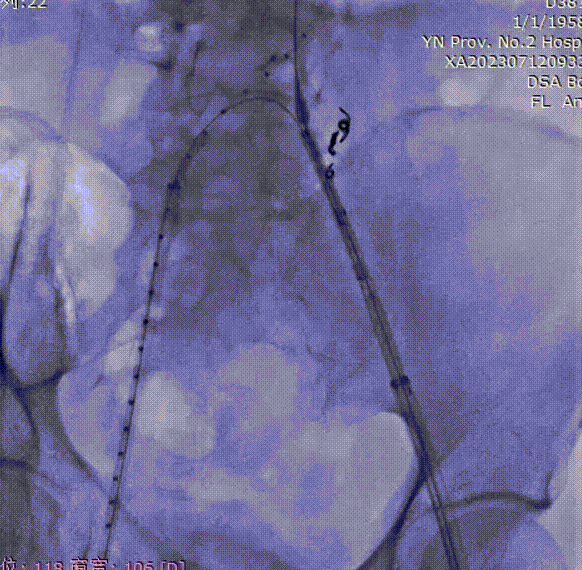

导管内手推造影,确认右髂内超选成功;

gore医疗怎么样「漫腹精论」双股动脉入路,纯腔内保双髂——GORE® EXCLUDER® 髂动脉分支型覆膜支架(IBE)治疗双侧髂总动脉_https://www.jmylbn.com_新闻资讯_第23张

右髂内支架通过IBE短腿后,整体往下拉IBE,将IBE短腿拉至右髂内动脉开口上方;